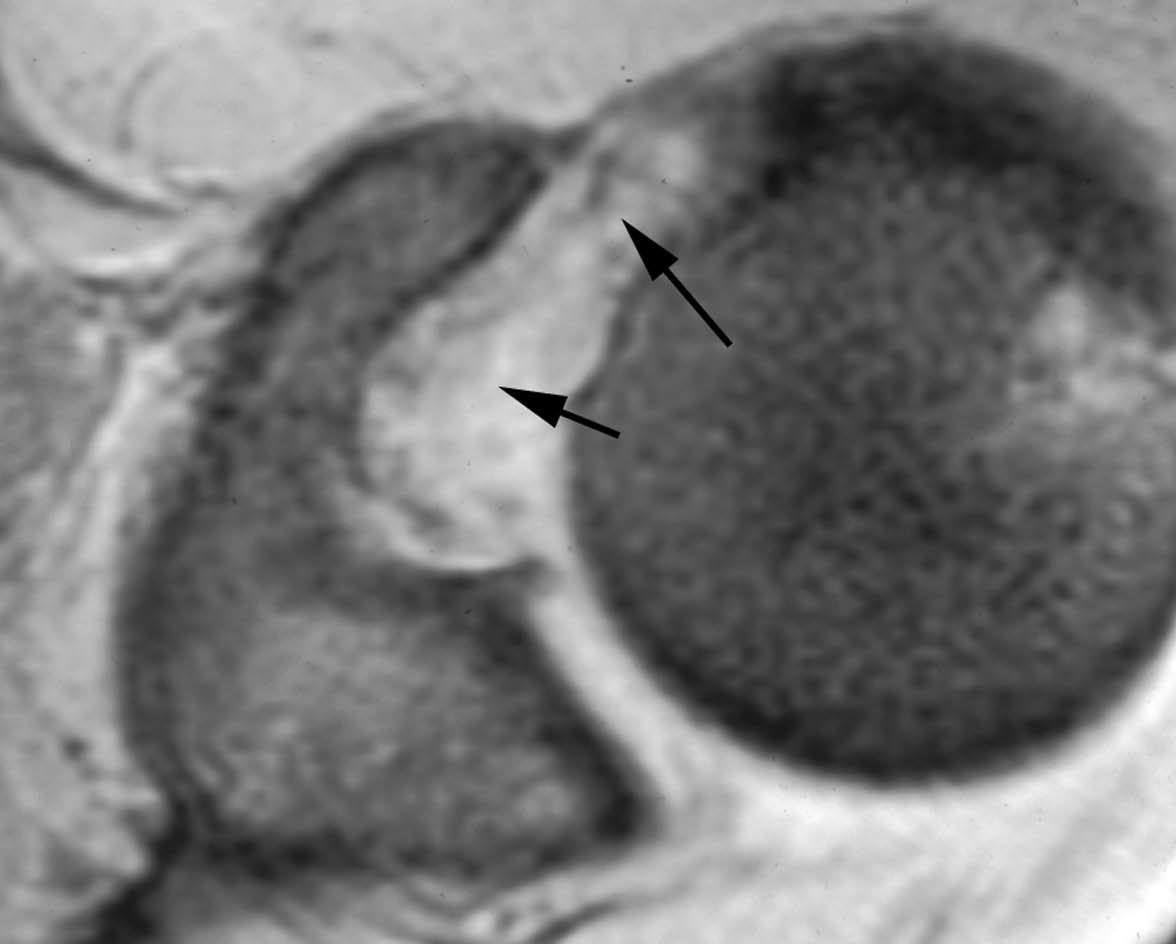

GLAD (gleno labral articular disruption)

El GLAD puede acompañar a cualquiera de las patologías que se discuten en este artículo, afectando al LG. Se trata de una disrupción de un fragmento de cartílago articular junto a la lesión del LG20 (fig. 16).

Fig. 16.--Lesión de GLAD (gleno labral articular disruption). Artrorresonancia axial T1 con supresión grasa donde se puede observar una rotura del labio glenoideo anterior y posterior (flecha). El labio glenoideo anterior está más desplazado. Se ve un fragmento de cartílago articular separado de su posición normal en la cavidad glenoidea y adherido al labio glenoideo anterior (cabezas de flecha).